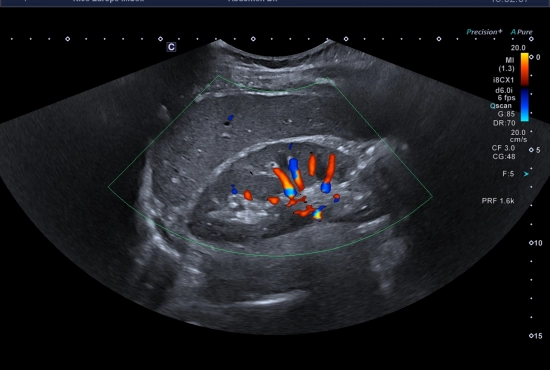

"Quand une douleur testiculaire cache une hernie inguinale : l'importance de l'exploration systématique des orifices herniaires"

25/04/2026

Lire la suite